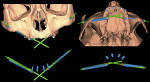

To evaluate whether the actual surgical placement of the zygomatic implants matched the computerized planning and simulation, the preoperative positions must be compared with the postoperative implant positions. Merging the preoperative CT scan data with the postoperative CT after implant placement makes it possible to measure the degree of accuracy of the superimposition using sophisticated software (Figure 19 through Figure 22).31

The procedure was accomplished as follows: First, extraction/conversion and segmentation was performed to export the STL files of the surface bone reconstructed volume analysis and the actual implants from both the original 3D planning project and the postoperative CT scan using two specific software applications (RealGUIDE 5.0, 3Diemme srl, 3diemme.it; Mimics, Materialise). Second, superimposition and registration of the common bony parts not modified by surgery was performed to acquire the simulated implant designs and those actually positioned in a comparable position. Third, the STL file of every implant extracted from the postoperative CT is often characterized by metal scattering, which determines poor quality and low resolution of the images; therefore, this file was substituted with the STL file of the corresponding implant in the software library (using Geomagic Studio 12, Geomagic Inc, 3dsystems.com). Fourth, math calculation was performed, comparing, in millimeters and degrees, the deviation in correspondence to the base and apex for each pair of implants in the two situations that were computer planned, and then post surgery (Figure 23).

Using the superimposition of the pre- and postoperative CT scans, the positions of the 10 zygomatic implants were evaluated. The results of this evaluation are reported in Table 1 and Table 2. Because two different types of software were used with two different procedures to analyze the results, two separate tables are provided to report an overall statistical calculation of the results.

The following average values were obtained: In "Table 1, Values of Apical and Coronal Deviations…"the apical deviations were recorded as 2.11 mm; the coronal deviations were recorded as 3.55 mm; and the angular deviations were 4.55 degrees. In Table 2, the values recorded were as follows: apical deviations, 2.99 mm; coronal deviations, 2.96 mm; angular deviations, 1.88 degrees. Thus, deviations from the computerized/simulated project were between 2 mm and 3 mm, and angular deviations were between 1.88 and 4.55 degrees.

The preliminary results have been evaluated and appear to be quite favorable with regard to angular deviation values. The values of some horizontal deviations, however, may relate to an imperfect placement of the surgical guide (Figure 19 through Figure 22; Table 1 and Table 2). Apart from the mathematical measurements, the images of the superimposition illustrate in every case good correspondence between the inserted implants and those planned, and, importantly, no implants damaged any adjacent vital anatomical structures.